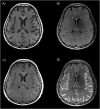

Methods: Patients with biologically-confirmed COVID-19 and neurological manifestations undergoing a brain MRI with technically adequate arterial spin labeling (ASL) perfusion were included in this retrospective multicenter study. ASL maps were jointly reviewed by two readers blinded to clinical data. They assessed abnormal perfusion in four regions of interest in each brain hemisphere: frontal lobe, parietal lobe, posterior temporal lobe, and temporal pole extended to the amygdalo-hippocampal complex.

Results: Fifty-nine patients (44 men (75%), mean age 61.2 years) were included. Most patients had a severe COVID-19, 57 (97%) needed oxygen therapy and 43 (73%) were hospitalized in intensive care unit at the time of MRI. Morphological brain MRI was abnormal in 44 (75%) patients. ASL perfusion was abnormal in 53 (90%) patients, and particularly in all patients with normal morphological MRI. Hypoperfusion occurred in 48 (81%) patients, mostly in temporal poles (52 (44%)) and frontal lobes (40 (34%)). Hyperperfusion occurred in 9 (15%) patients and was closely associated with post-contrast FLAIR leptomeningeal enhancement (100% [66.4%-100%] of hyperperfusion with enhancement versus 28.6% [16.6%-43.2%] without, p = 0.002). Studied clinical parameters (especially sedation) and other morphological MRI anomalies had no significant impact on perfusion anomalies.

Conclusion: Brain ASL perfusion showed hypoperfusion in more than 80% of patients with severe COVID-19, with or without visible lesion on conventional MRI abnormalities.